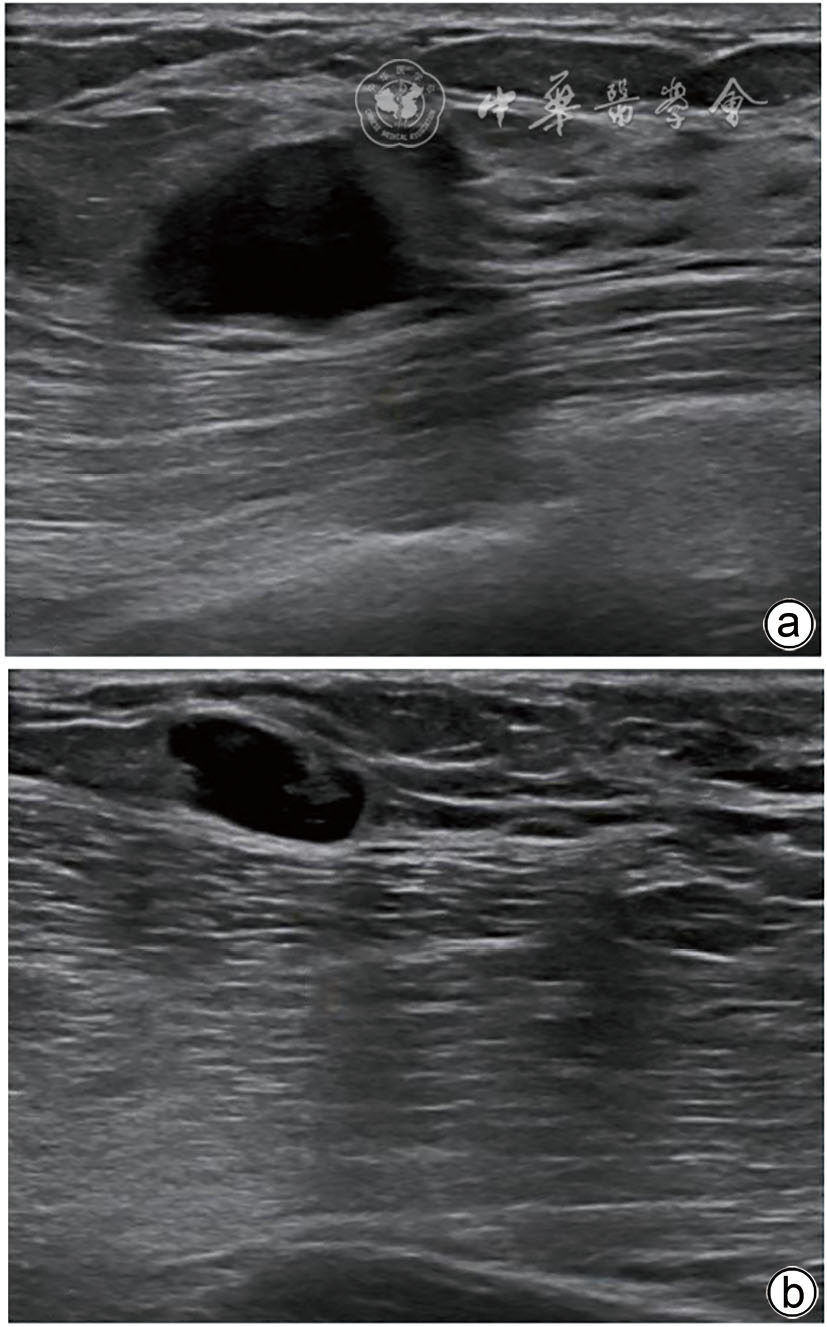

图1 乳腺转移性黑色素瘤患者乳腺超声图像 a图为右乳肿块 ;b图为右侧腋窝淋巴结